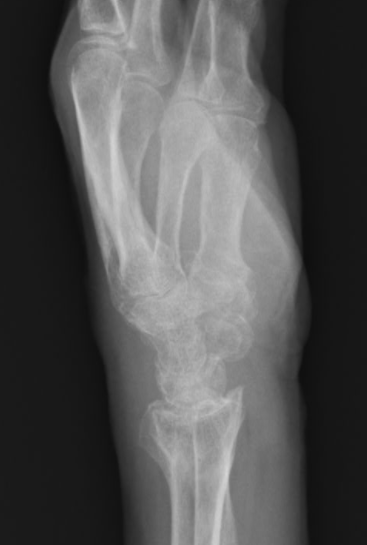

55歳、女性、テニスのプレイ中に転倒して手首骨折。

嫁ぎ先のニュージーランドでボルトで骨折部の接合を行ったが疼痛が徐々に増強。ボルトがゆるんでいることが判明し即切除。その後、固定期間が長く日常生活にはほとんど支障はないが、感覚の左右差があり不快感が解消されない

一時帰国の際に当院を選択し、PNF、皮膚刺激による手技にて、硬結、瘢痕組織が消失(約1時間の時間を要した)して関節の可動域が左右差なく改善された。

患者に通院していたクリニックでの画像診断を指導し、担当医から現在の状況と今後の加療についての報告を以下の画像と共に持参。

傷病名

左橈骨遠位端骨折、左手指骨萎縮、骨粗しょう症、慢性疼痛

既往歴

デュプイトラン拘縮術後

症状経過および検査結果

2021.10.20. 転倒にて左橈骨遠位端骨折受傷。他院にて整復、ギプス加療されたようです。途中特に理学療法う等施行されず2021.11.26当院に受診されました。

初診時骨癒合認めるも。橈骨短縮橈側転位残存、尺骨突き上げを認める。理学療法にて手関節可動域向上しましたが、回内回外の制限及び手指拘縮が改善せず、長期固定に伴い(固定中は一度も促通等施していなかったようです)筋腱膜の癒着、滑走障害、手根骨の可動性低下等、様々な要因が複合的に重なり現在の症状を呈していると考えます。一度超音波上の筋膜リリース等施行してみる予定(3/15)です。また、手根骨の可動性の確認(3/16予定)も併せて施行します。

今後貴院にてご加療を希望されており、一度診療情報提供させて頂きました。宜しくお願い致します。